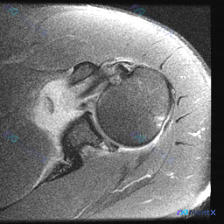

看到一个肩关节病例,临床怀疑盂唇病变,但只提供了一张轴位T2加权MRI图像。先看影像分析结果: 轴位MRI表现: - 前、后盂唇形态基本完整,信号均匀,未见明确撕裂信号 - 肩胛下肌腱、冈下肌腱、肱二头肌长头腱信号正常,未见撕裂 - 肱骨头与关节盂对位良好,骨质及软组织未见明显异常 核心矛盾:临床怀...

最近看到一个肩关节MRI轴位T2序列的病例,患者临床怀疑有盂唇病变,但影像分析结果显示: - 前、后盂唇形态完整,呈典型三角形低信号 - 未见明显断裂、撕脱或异常高信号 - 肩胛下肌肌腱、肱二头肌长头腱形态及信号也正常 这种影像与临床不符的情况该怎么考虑?大家第一反应会往哪个方向走?